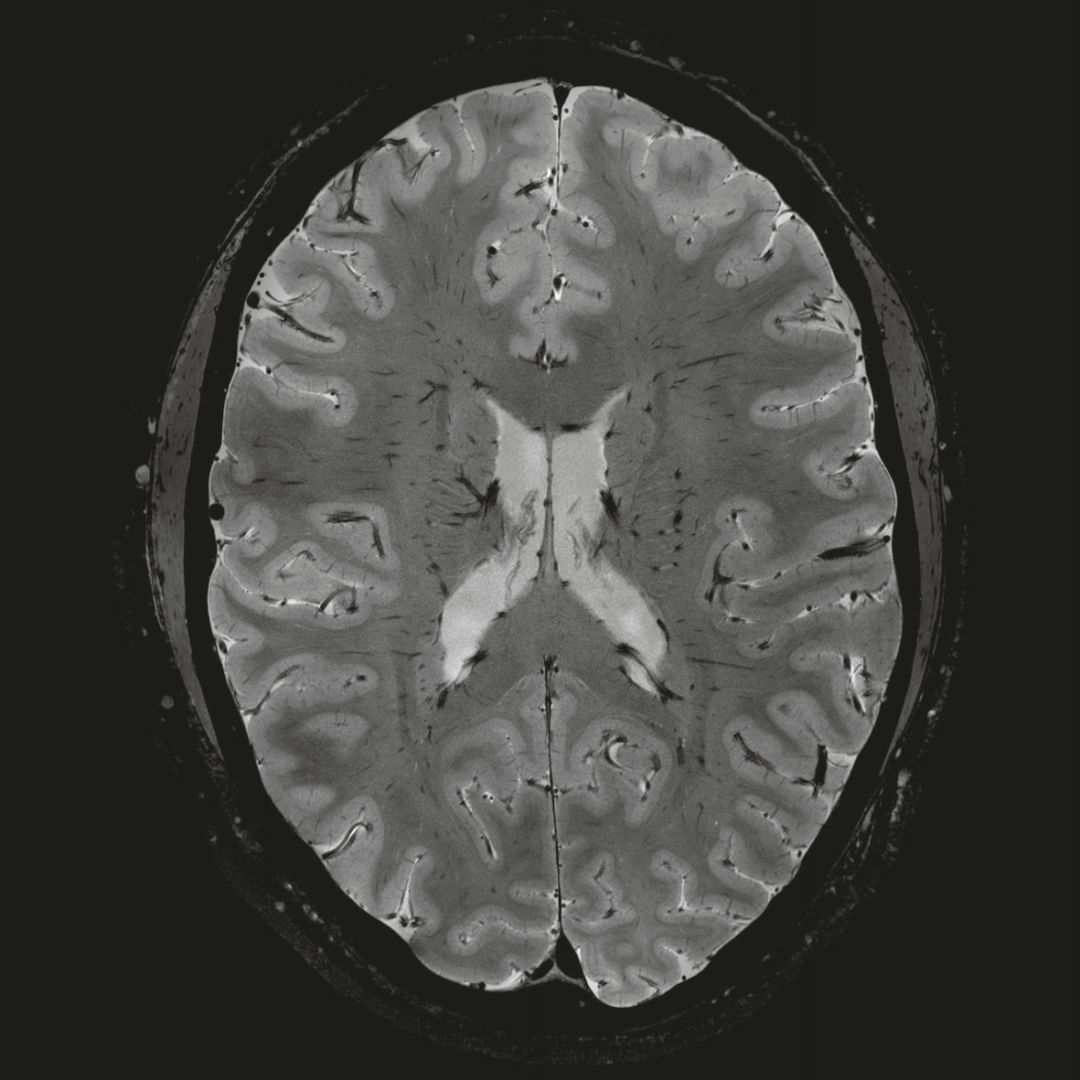

0.8毫米的各向同性分辨率:精確劃分灰質(zhì)和白質(zhì)

超精細的解剖細節(jié):T2對比

0.17 x 0.17 x 0.8毫米分辨率超高。